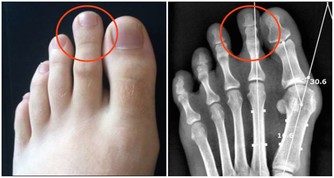

痛風患者

花生中嘌呤物質的含量高達79毫克/百克,

但如果患者正處於急性發作期時,最好還是